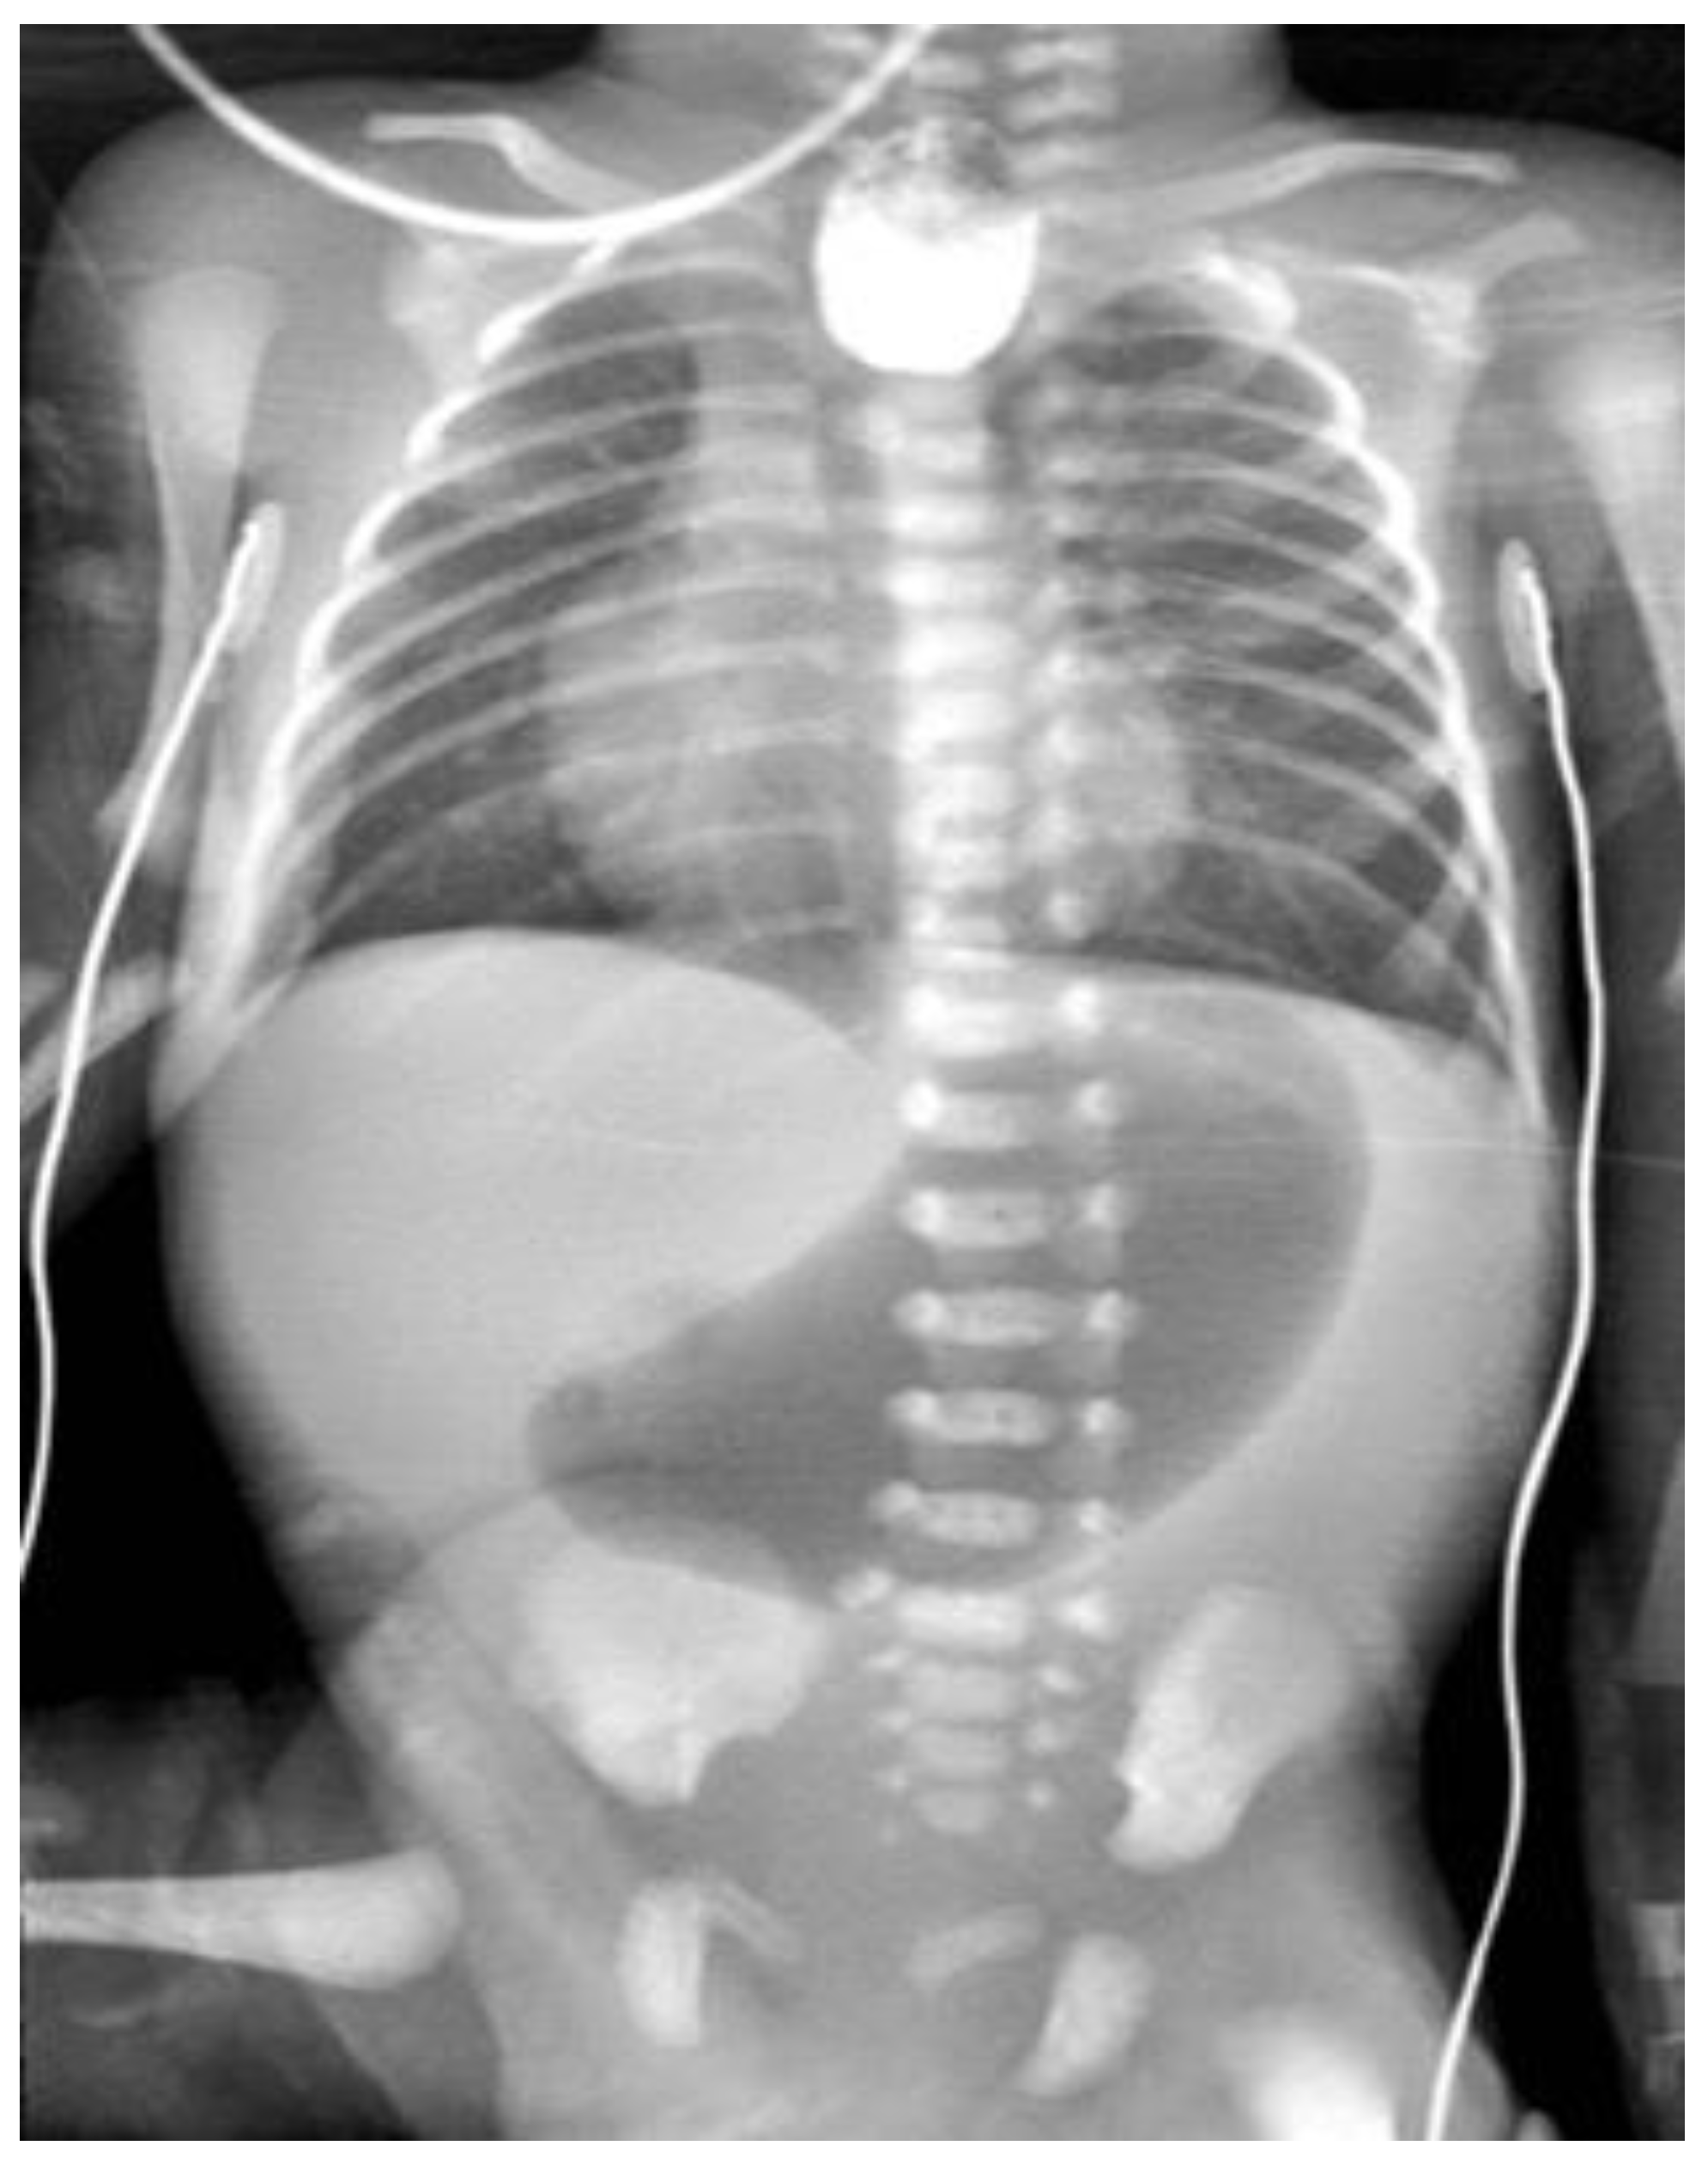

EA associating congenital microgastria: case 7